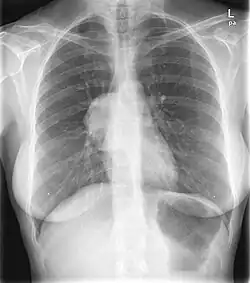

Hilum overlay sign

The hilum overlay sign is an imaging appearance on chest radiographs in which the outline of the hilum can be seen at the level of a mass or collection in the mid chest.[1] It implies that the mass is not in the middle mediastinum, and is either from anterior or posterior mediastinum(most of the masses arise from the anterior mediastinum).[2]